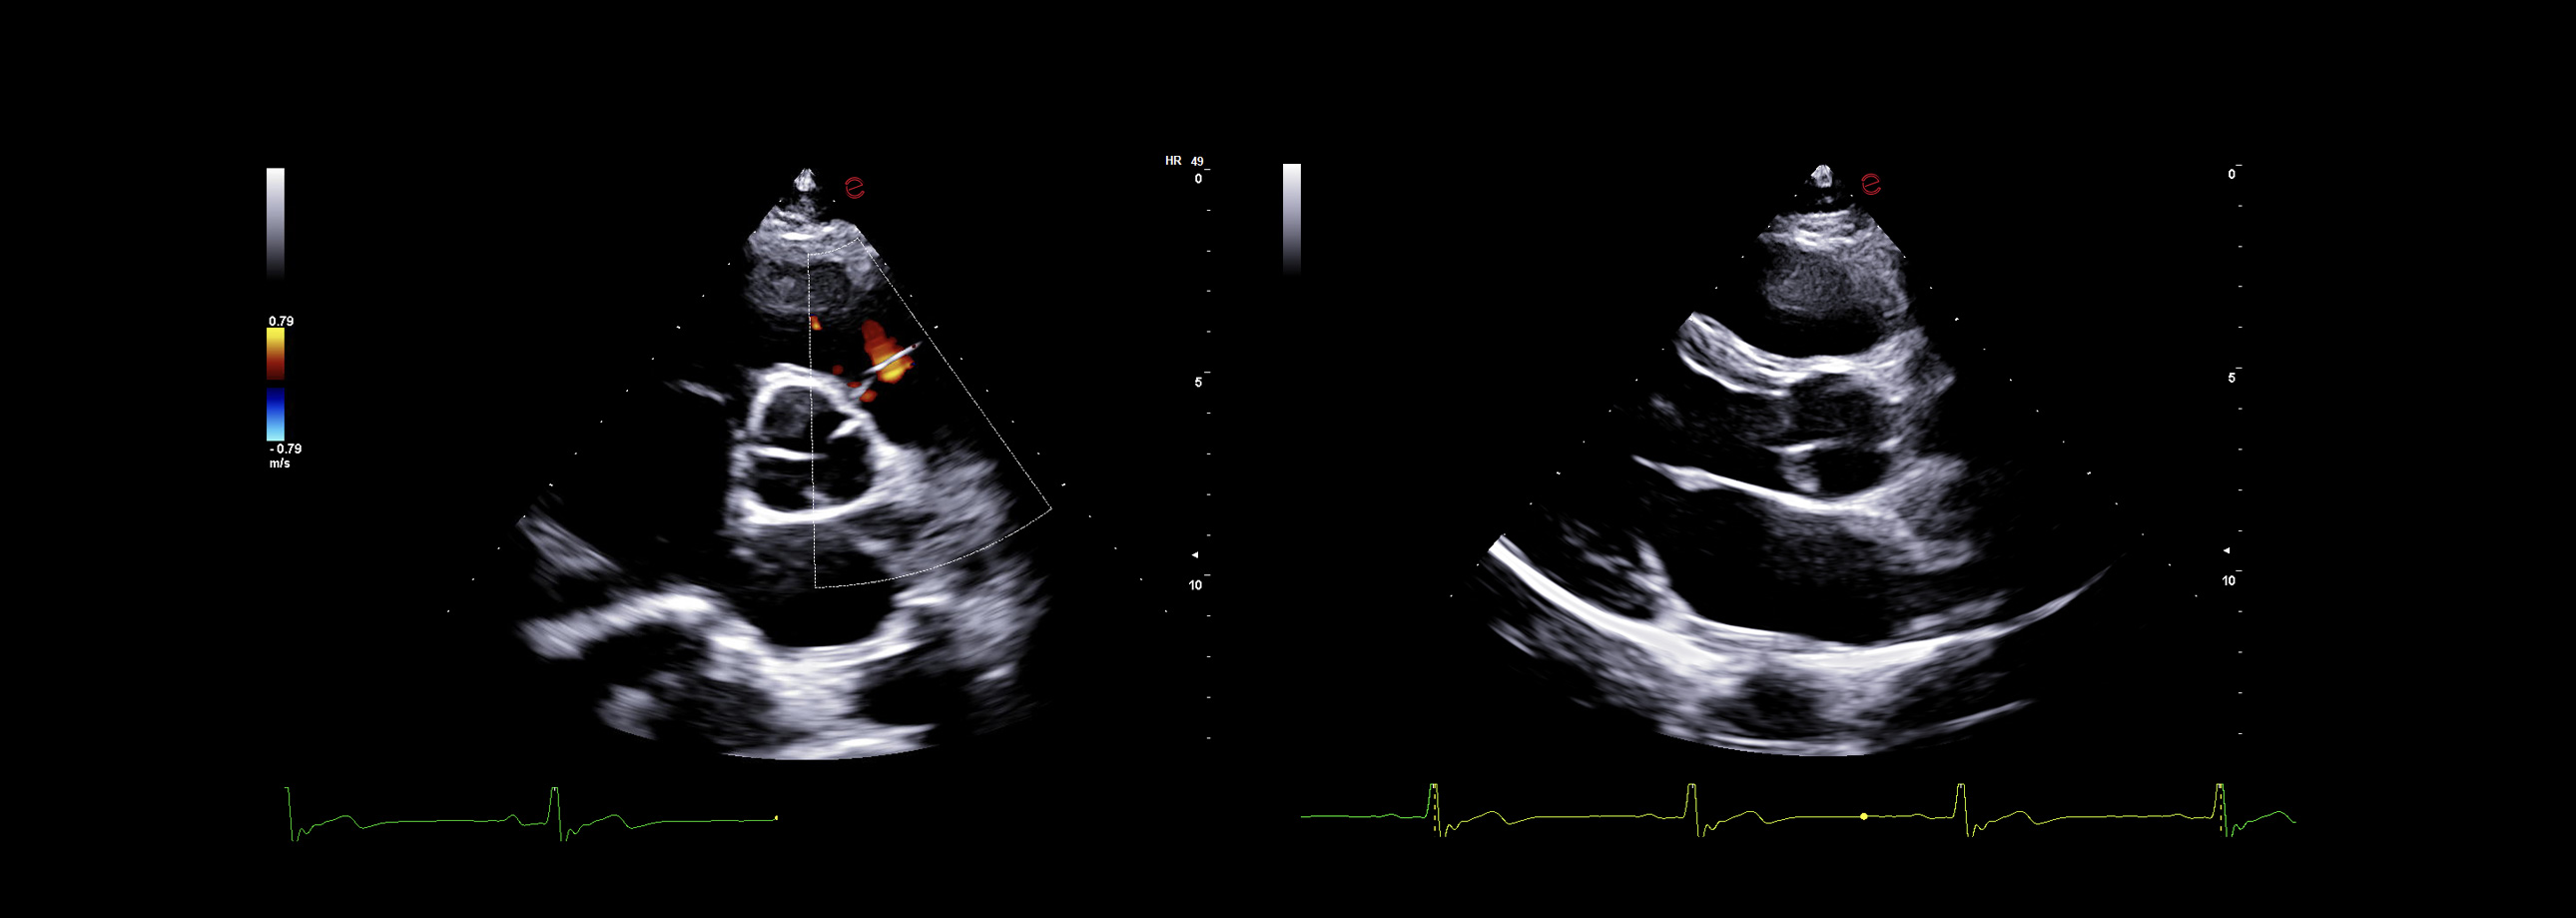

Innovative hemodynamic assessment with HyperDoppler

Esaote’s HyperDoppler technology provides an advanced visualization of intracardiac blood flow dynamics, offering clinicians an intuitive understanding of complex hemodynamics that goes beyond conventional Doppler imaging. By generating real-time vector maps, streamlines, and vortex formations, HyperDoppler enables the detailed assessment of diastolic function, ventricular dyssynchrony, and valvular abnormalities.

This unique flow visualization supports earlier detection of subtle dysfunction, particularly in challenging cases such as heart failure, prosthetic valve evaluation, and structural heart disease. HyperDoppler’s zero-click, visually rich interface enables faster, more comprehensive exams, allowing cardiologists to make more informed clinical decisions.